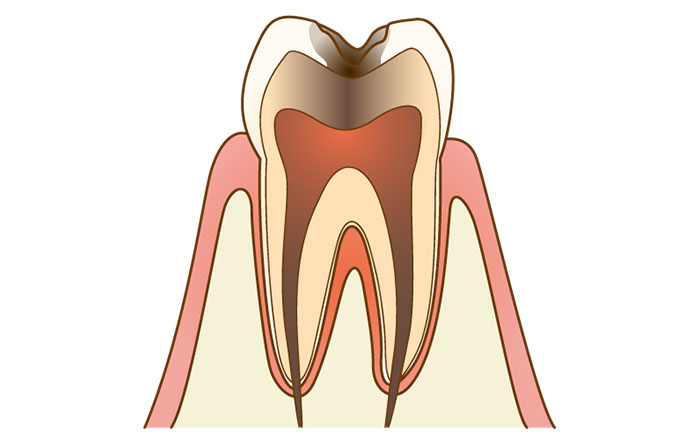

4.C3のむし歯

C3のむし歯は、歯髄という歯の神経にまで達したむし歯の状態です。歯根膜に炎症が起こって歯に大きな穴が空き、何もしなくてもズキズキと痛みます。